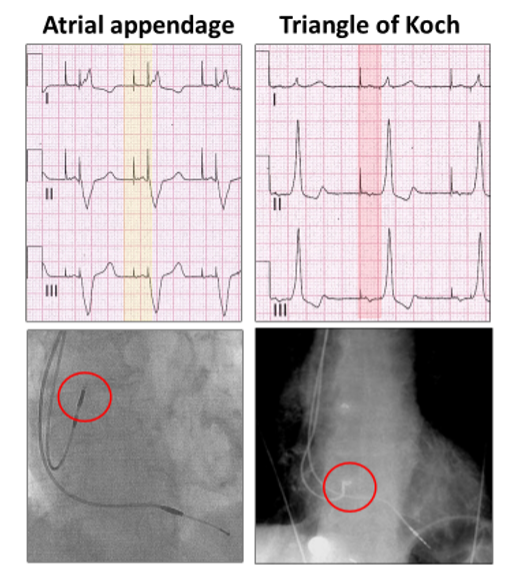

High atrial pacing has a normal P wave axis (yellow highlight), whereas with pacing from the triangle of Koch at the mouth of the coronary sinus, the wave of depolarization is toward the left shoulder and P waves inverted in leads II and III (red highlight).

Atrial pacing is very low in the atrium.

However, not all atrial paced beats are conducted (red highlight), because of the intermittent AV block:

There appears to be ventricular paced beats as well (yellow highlight).